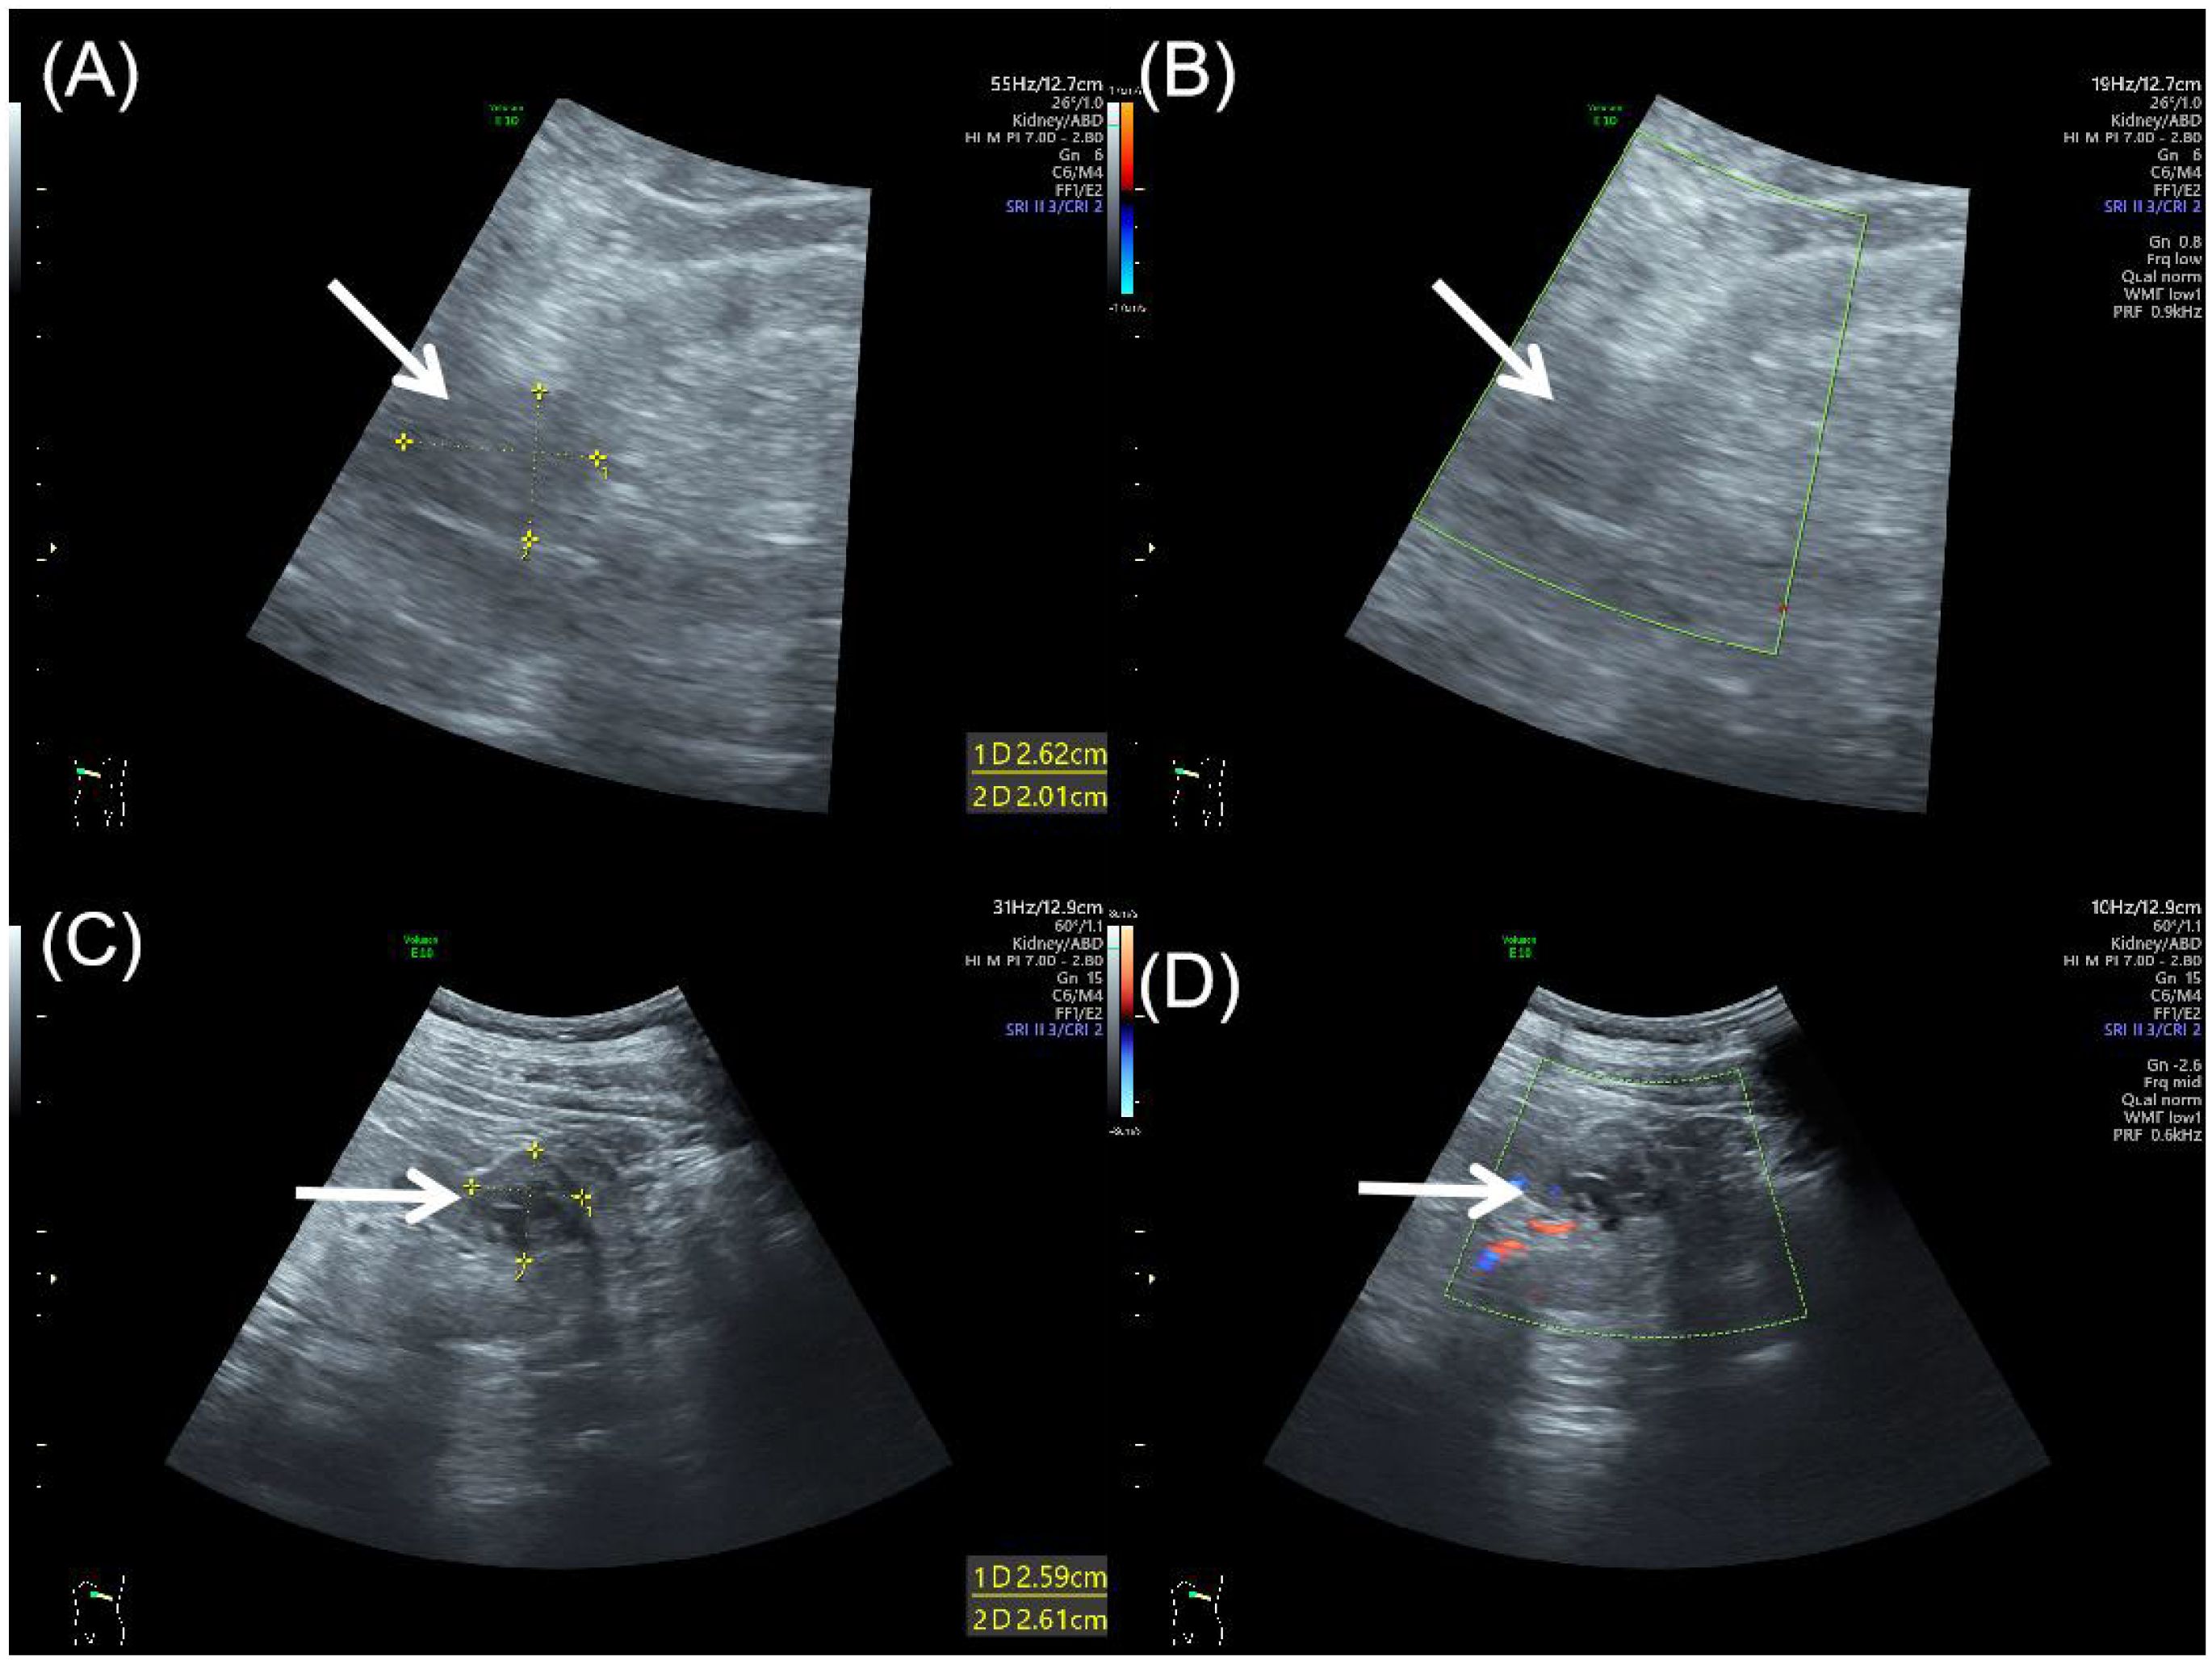

Background: This report presents an exceptionally rare case of bilateral synchronous renal tumors comprising papillary renal neoplasm with reverse polarity (PRNRP) and renal cell carcinoma with fibromyomatous stroma (RCC-FMS) in a single patient. No prior cases of this specific combination occurring synchronously and bilaterally have been reported. Case Presentation: A 65-year-old man presented with incidentally detected bilateral renal masses. Abdominal ultrasound and contrast-enhanced computed tomography (CT) revealed distinct imaging characteristics for each tumor. The right kidney mass was exophytic, heterogeneous, and hypovascular on ultrasound, showing marked heterogeneous enhancement with hypoenhancing foci on CT. The left kidney mass was a well-circumscribed, mixed-attenuation nodule with peripheral/septal enhancement on CT. The patient underwent bilateral laparoscopic partial nephrectomy. Histopathological and immunohistochemical analysis confirmed PRNRP in the right kidney (CK7+, GATA3+, Ki-67 approximately 2%) and RCC-FMS in the left kidney (PAX-8+, CA IX+, CD10+, Ki-67 approximately 3%). Real-time quantitative-PCR testing was positive for a KRAS exon 2 mutation, but was negative for NRAS (exons 2-4) and BRAF V600 (exon 15) mutations. Conclusion: This represents the first documented case of synchronous bilateral occurrence of PRNRP and RCC-FMS. It highlights significant diagnostic challenges due to overlapping imaging features with more common renal tumors. It underscores the critical role of multimodal imaging (ultrasound, CT) combined with meticulous histopathology, immunohistochemistry, and molecular genetic analysis for accurate diagnosis. The generally indolent nature of both tumors supported successful nephron-sparing surgical management. This unique case emphasizes the need for a high index of suspicion for rare tumor subtypes and a multidisciplinary approach to optimize the diagnosis and tailored treatment of complex renal masses.